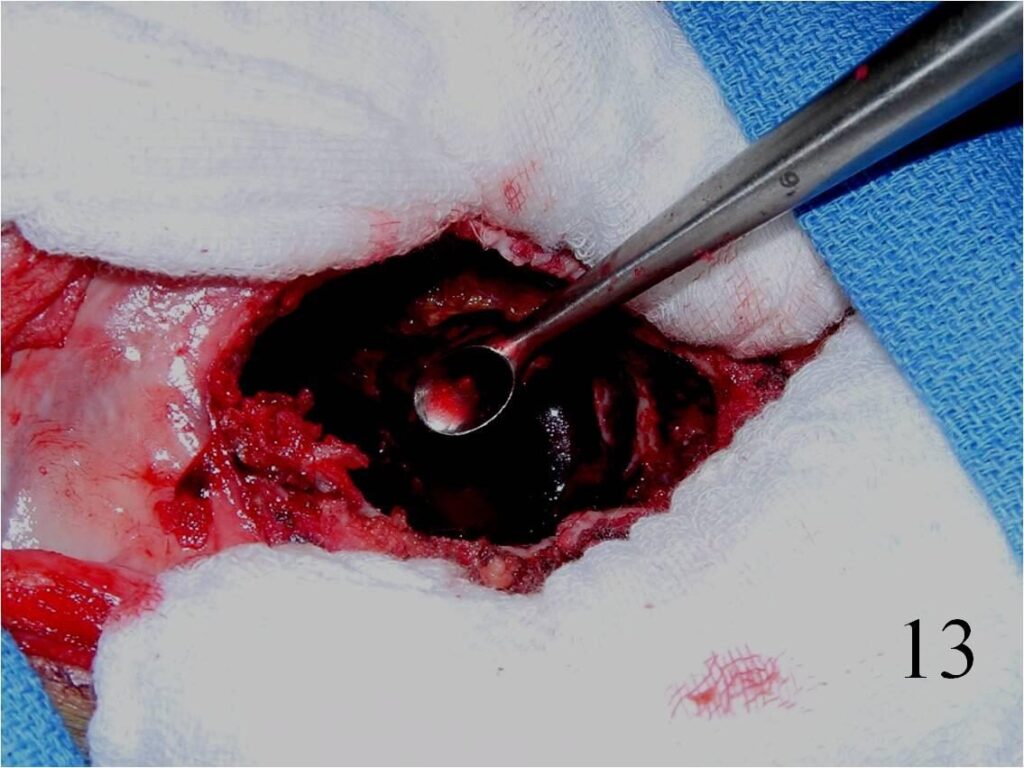

o Dr. Wittig’s preference is to perform an extensive curettage resection where the tumor is curetted and the tumor cavity shaved with a high speed burr wherever possible. The cavity is then subjected to cryosurgery that involves the direct application of liquid nitrogen to eradicate microscopic tumor cells. The cavity is usually fixed with a combination of cement and an internal fixation device. Bone graft may be utilized to bone graft the subchondral plate if necessary. Results with cryosurgery have had the lowest recurrent rates reported thus far.

o Curettage, cement and possible internal fixation with hardware (Fig. 13, 14, 16)

Fig. 13 Intralesional curettage of the giant cell lesion and (Fig. 14) shaving the wall of the tumor cavity with high speed burr.